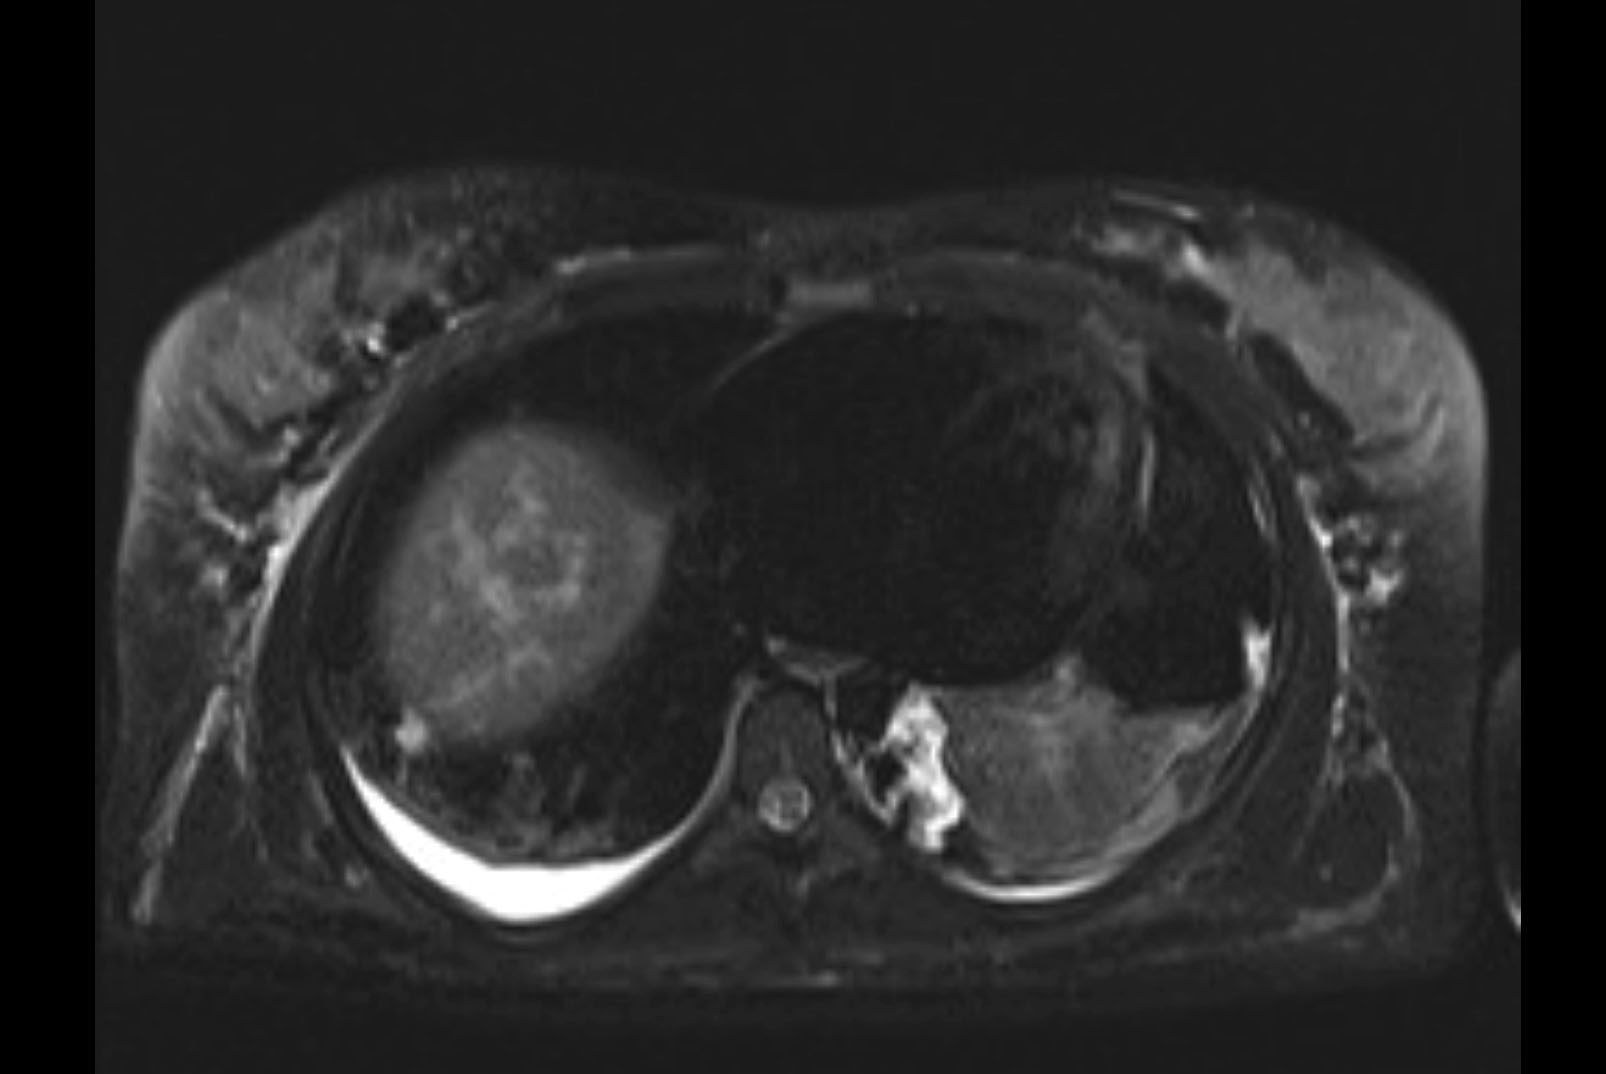

MRI T1

MRI T2

Imaging analysis

Based on initial findings, which issue(s) would you be most concerned about?